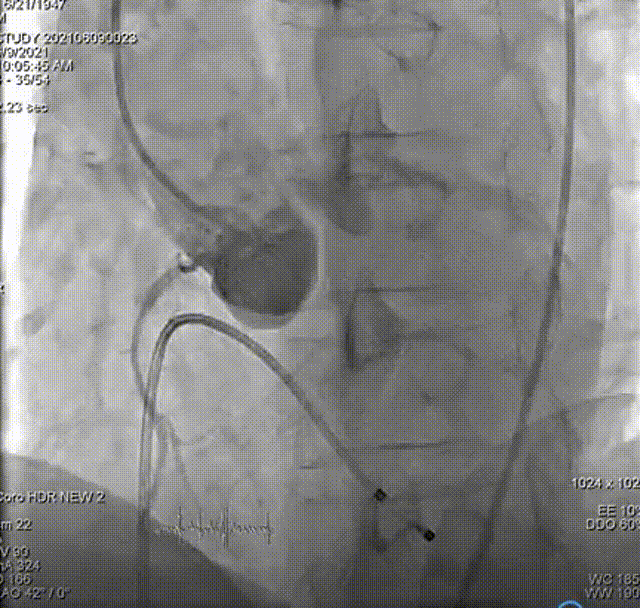

主动脉根部造影,双侧冠脉血流未见明显异常。

输送系统输送至窦底,行主动脉根部造影,借助无冠窦猪尾造影定位,由于该患者基础心率较缓慢,瓣膜无起搏顺利释放。

术后心电监护未见传导阻滞。即刻造影和测压显示基本无压差和无反流。